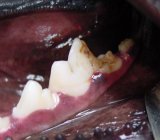

Restoration of enamel defect

Finished composite restoration of lower first molar. This case was submitted by Dr. Bert Dodd of Austin, Texas.